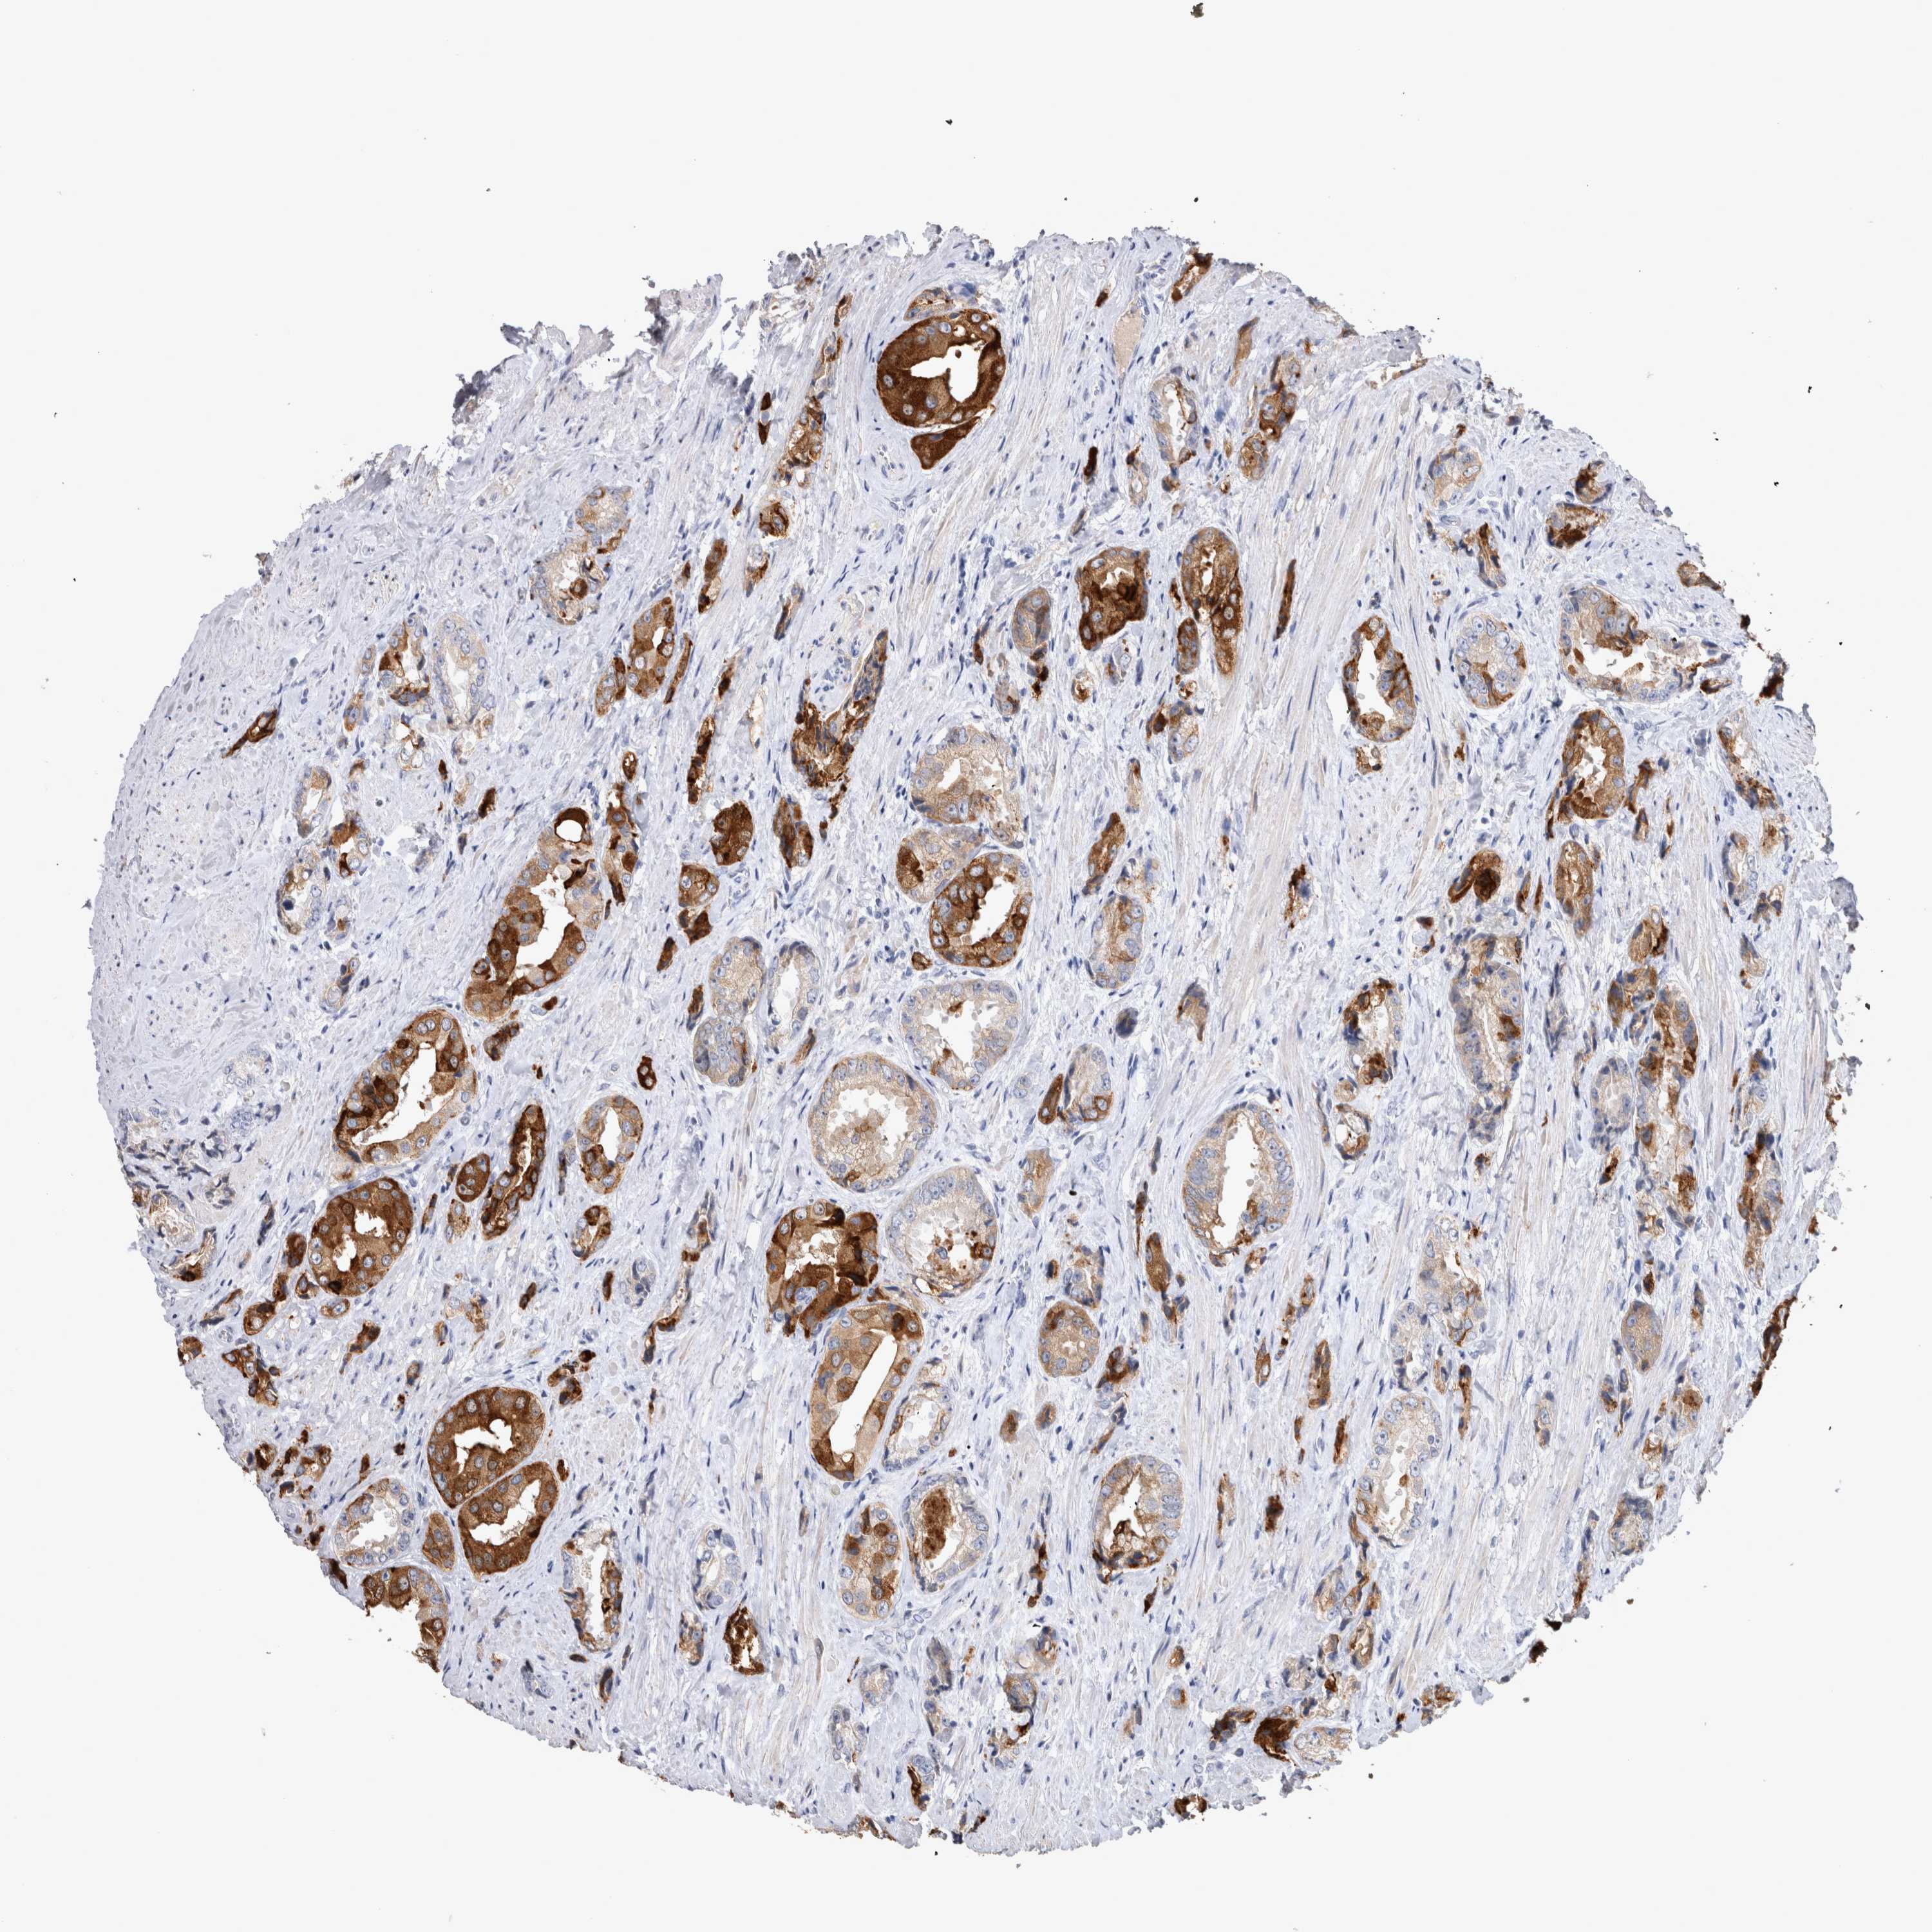

PROSTATE CANCER - Protein expressioni

A mouse-over function shows sample information and annotation data. Click on an image to view it in a full screen mode. Samples can be filtered based on level of antibody staining by selecting one or several of the following categories: high, medium, low and not detected. The assay and annotation is described here.

Antibody stainingi

Antibody staining in the annotated cell types in the current human tissue is reported as not detected, low, medium, or high, based on conventional immunohistochemistry profiling in selected tissues. This score is based on the combination of the staining intensity and fraction of stained cells.

Each image is clickable and will lead to virtual microscopy that enables deeper exploration of all samples and also displays staining intensity scores, fraction scores and subcellular localization as well as patient and tissue information for each sample.

Antibody HPA051257

Antibody CAB026357

Staining

High

Medium

Low

Not detected

Intensity

Strong

Moderate

Weak

Negative

Quantity

>75%

75%-25%

<25%

None

Location

Nuclear

Cytoplasmic/membranous

Cytoplasmic/membranous,nuclear

Adenocarcinoma, High grade

Adenocarcinoma, Medium grade

Adenocarcinoma, Low grade